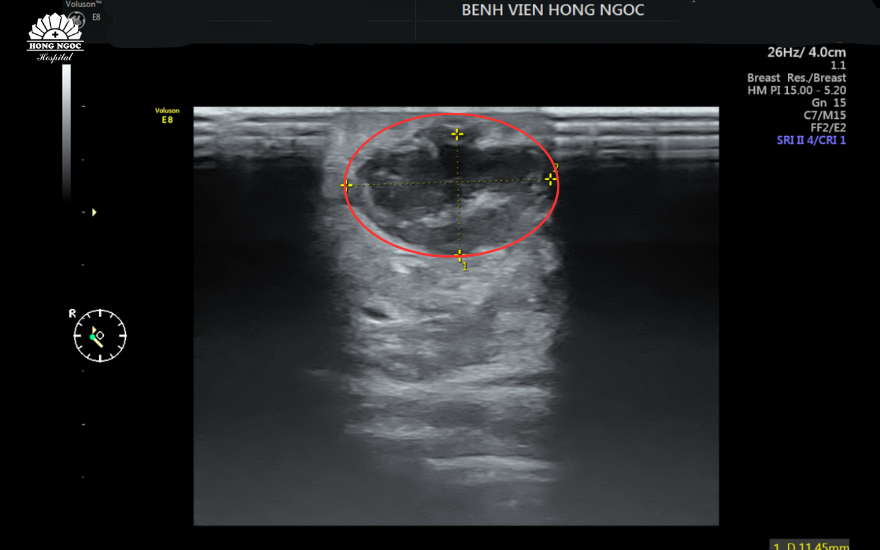

Trong quá trình thăm khám, các bác sĩ thấy phần vú phải của chị L có khối sưng nóng kích thước 3x3cm, siêu âm tại vị trí 1/4 dưới ngoài sát núm vú có khối dịch kích thước 11x19mm, tăng sinh mạch xung quanh. “Đây là biểu hiện điển hình nhất của tình trạng áp xe vú, cần thực hiện chích áp xe, dẫn lưu mủ ngay để giảm tối đa biến chứng đến sức khỏe của bệnh nhân.” BSCKI Đoàn Ngọc Minh (Khoa Sản Phụ khoa - BVĐK Hồng Ngọc) cho biết.

Hình ảnh khối áp xe vú kích thước 11mm tại quầng vú phải của chị L.